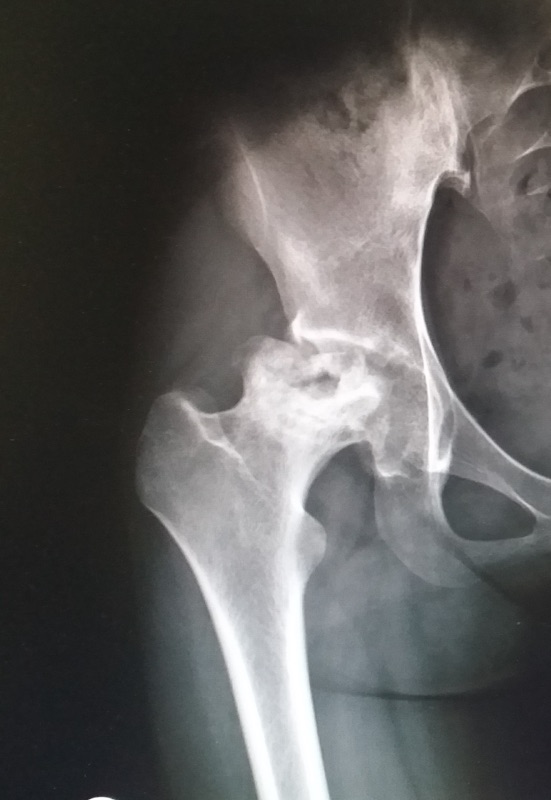

เมื่อโรคพัฒนาเข้าสู่ AVN ระยะที่ 4 (Stage IV) ถือเป็น “ระยะท้าย” ของโรคที่หัวกระดูกยุบอย่างชัดเจนและข้อสะโพกเสื่อมรุนแรง ในระยะนี้วิธีรักษาที่ได้ผลที่สุดและยั่งยืนคือ การผ่าตัดเปลี่ยนข้อสะโพกเทียม (Total Hip Replacement: THR)

ถ้ามีอาการดังกล่าวและภาพ MRI หรือ X-ray แสดงการยุบของหัวกระดูก แพทย์มักแนะนำให้ผ่าตัด

วางแผนด้วยภาพ X-ray/MRI เพื่อเลือกขนาดอุปกรณ์อย่างเหมาะสม

หากเอกซเรย์หรือ MRI บอกว่ากระดูกยุบแล้ว และอาการปวดรบกวนชีวิตมาก การผ่าตัด THR คือทางเลือกมาตรฐานที่ปลอดภัย มีประสิทธิภาพ และผลดีในระยะยาวครับ